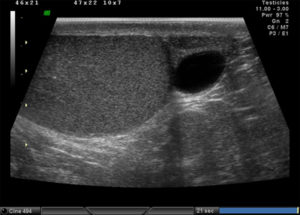

Гидроцеле

При данной патологии между двумя листками оболочки яичка происходит накопление жидкости. Водянка может быть приобретенная, чему способствует целый ряд факторов и врожденная, что обуславливается врожденными анатомическими дефектами.

Приобретенная водянка, как правило, появляется после воспалительных процессов, травм мошонки, оперативных вмешательств. При ультразвуковом осмотре диагностировать скопление жидкости между оболочками не представляет особых трудностей. Водянка на сонограмме выглядит, как анэхогенная зона вокруг яичка и его придатка. У некоторых пациентов встречается многокамерная водянка или в виде восьмерки (если жидкость скапливается и в паховом канале).